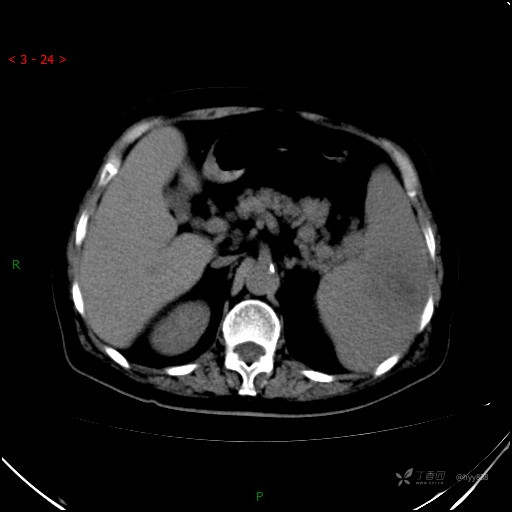

上腹部CT平扫